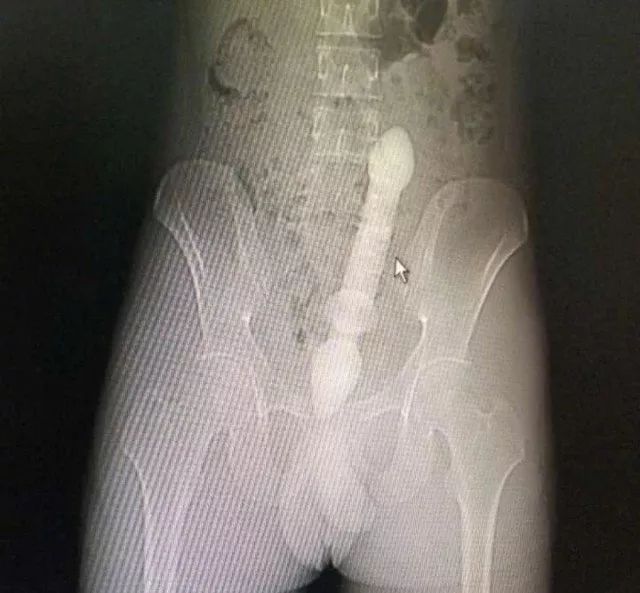

CT三维重建下三条泥鳅的骨骼清晰可见

占据整个下腹部和盆腔......

2月10日那天我看的急诊,事情的经过是这样的,我是他的首诊大夫,一开始急诊打电话急会诊说是吃泥鳅吃坏了肚子,我觉得这也没啥,然后让他做腹部CT。后来看到他的CT赫然三条鱼骨头。我一看CT很吃惊,难道是生吃的?

去一楼急诊问患者本人,当时我听他说了事实,是下面塞进去的真把我吓一跳。他第一句话就是说,听信网上前列腺偏方把他害惨了,让我救救他赶紧手术,问我有没有穿孔,当时只有一个小时,还早,摸着板状腹很硬。他意识还有,后来就慢慢感染中毒休克了。后来术中发现乙状结肠穿孔,三条鱼都到了腹腔里,有一条还往回盲部钻,不过取出来应该都是死的了。